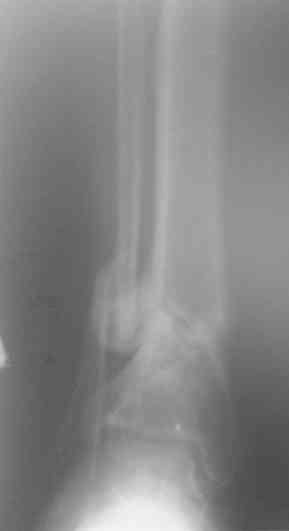

Уважаемые коллеги. 1.06.07 поступил солдатик, с огнестрельным сквозным ранением в н/3 левой голени. Огнестрельный перелом дистального отдела tibia. При поступлении АД 100/60. произведена обычная ПХО. Назначены антибиотики. Рана задренирована (пока что турунды с фурацилином). За последние сутки отмечался несколько раз подъем темп-ры до 38,5. Получает инфузионную терапию, цефазолин, линкомицин, добавили метрогил. Подскажите дальнейшую тактику ведения. И еще, что очень важно для нашего учреждения, возможные способы обезболивания при перевязке.

У меня сейчас лечится похожий пациент - ему стрельнули в упор из охотничьего ружья: открытый скозной перелом правой голени в н/3 с дефектом костной ткани до 6 см. При поступлении наложили ап.Илизарова. После отторжения всех некрозов и несмотря на сохраняющиеся раны (чтобы не терять время) мы провели повторную операцию - наростили аппарат Илизарова вверх на одно кольцо, под которым сделали поперечную остеотомию большеберцовой кости (в проксимальном метафизе) и теперь низводим образовавшийся промежуточный фрагмент по 1-2 мм в сутки при сохранении общей длины конечности. В месте остеотомии растет регенерат, который постоянно рентген-контролируем. Думаю что это самый лучший вариант для подобного рода травм. Если будет интересно могу показать снимки (как раз скоро очередной рентген-контроль).

3. Рентгенограммы